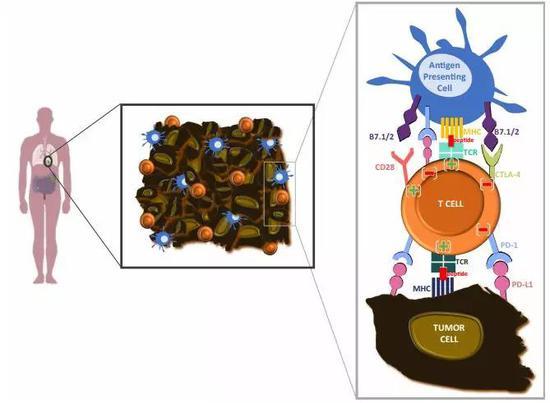

免疫疗法,能不能再次超越放化疗呢?从理论上来说,免疫新辅助治疗也有不少优势,比如手术前患者的免疫系统更加完整,只是被肿瘤操纵,进入了明显的免疫抑制状态[4]。这样的话,PD-1/L1抑制剂们就不容易放空枪。

而手术前使用O药,确实调动了患者体内的T细胞进入抗肿瘤免疫状态,病理切片也证实,大量的T细胞和巨噬细胞浸润到了肿瘤当中。患者的肿瘤突变负荷(TMB),则有望作为预估疗效的生物标记物[10]。

当然,机遇和挑战同在。拿生物标记物来说,肿瘤突变负荷(TMB),在CheckMate-159试验中就与患者的新辅助疗效有关,突变数量越多,疗效就相对越好,这也符合了免疫新辅助治疗利用大量新抗原的道理。

但是治疗晚期患者时有指导意义的PD-L1表达情况,在CheckMate-159试验和Tecentriq+化疗的试验中都没体现价值[13]。会不会还有其他的生化标记物,比如T细胞亚群,等待着后续试验的挖掘呢?

比如用药次数和时机,新辅助治疗用几个周期才性价比最高,还不耽误手术的时间?而在免疫新辅助治疗时代,唱主角的也肯定不止PD-1/L1抑制剂们,搭配化疗药、抗CTLA-4单抗、抗血管生成药物甚至是放疗,也许都是有效的。

微环境里群魔乱舞,PD-1抑制剂也不一定能独撑危局